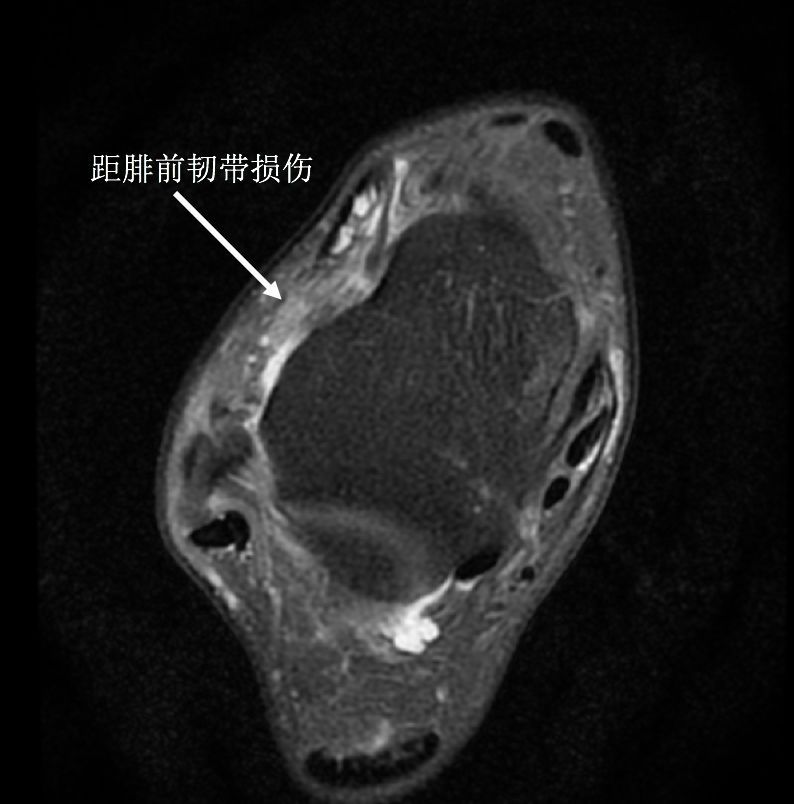

踝关节反复扭伤患者在追问病史时多可发现患者在首次踝关节受伤时会伴随有踝关节明显肿胀,这种表现往往代表维持关节稳定的外侧副韧带尤其是距腓前韧带损伤。但是很多人却认为不需特殊治疗,等待肿胀消退后就会自行好转,在首次受伤后没有得到及时的正规治疗,或者治疗方法不当,导致保护踝关节稳定的韧带没有愈合,从而使踝关节稳定性下降,导致踝关节更容易扭伤。很多人表现为走不平的路或者女性穿高跟鞋时候踝关节有明显的肿痛或者不稳定感觉,也有一部分人走路时会出现打软腿症状。

(踝关节距腓前韧带损伤)

(正常的距腓前韧带)